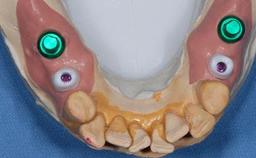

The patient presented with a failing tooth-supported fixed dental prosthesis with cantilever extension replacing the right maxillary central incisor. His chief presenting complaint was poor esthetics, in particular the dark discolored margin around the abutment tooth, the maxillary left central incisor. He reported a history of trauma at a young age, which necessitated the replacement of his maxillary right central incisor as well as root canal therapy of the adjacent left central incisor. The existing prosthesis had been in situ for over 20 years. The initial periapical radiograph displayed good proximal bone levels at the adjacent teeth and a wide incisive canal, which was a concern. The left central incisor presented a very wide root canal treatment with compromised radicular dentin thickness, which was a consideration in the decision between a new tooth-supported fixed dental prosthesis vs. an implant-supported prosthesis. After a lengthy discussion on the risks and benefits of both treatment options, the patient decided on a single-tooth implant replacement.

Bone Augmentation Simultaneous

Augmentation Materials Xenogenous

Soft Tissue Grafting Staged

Abutment Type Customized